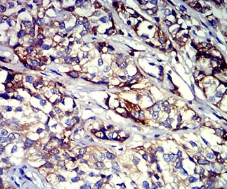

CD61 Mouse Monoclonal antibody[3E8A6]

IHC    1/200 - 1/1000